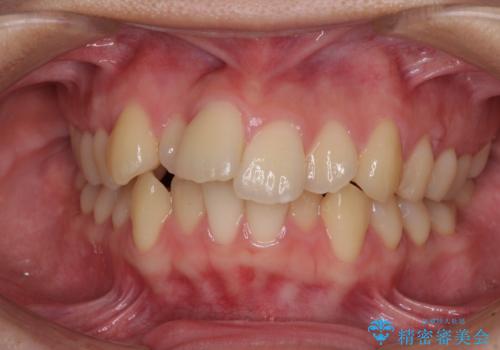

[ マウスピース矯正 ] 出っ歯に見える前歯を改善したい

![[ マウスピース矯正 ] 出っ歯に見える前歯を改善したいの症例 治療前](https://seimitsushinbi.jp/wp/wp-content/uploads/2023/10/IMG_6858-500x350.jpg?v=1697014973)

![[ マウスピース矯正 ] 出っ歯に見える前歯を改善したいの症例 治療後](https://seimitsushinbi.jp/wp/wp-content/uploads/2023/10/8a6c9bf89570c0c75da0a5fabd1cd70e-500x350.jpg?v=1697014858)